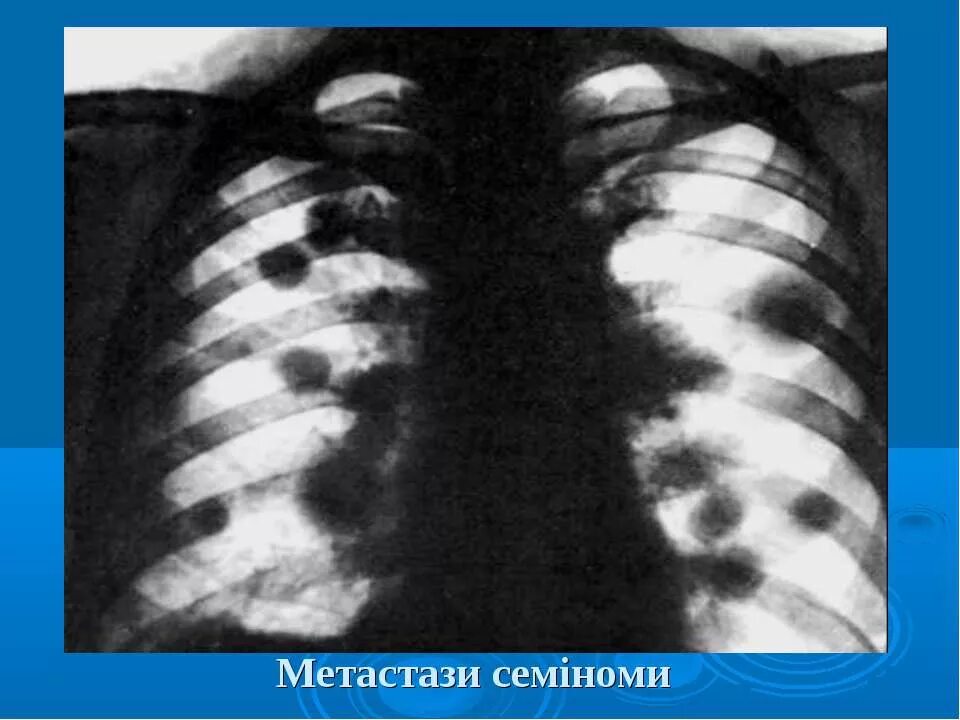

Метастазы в легких что это